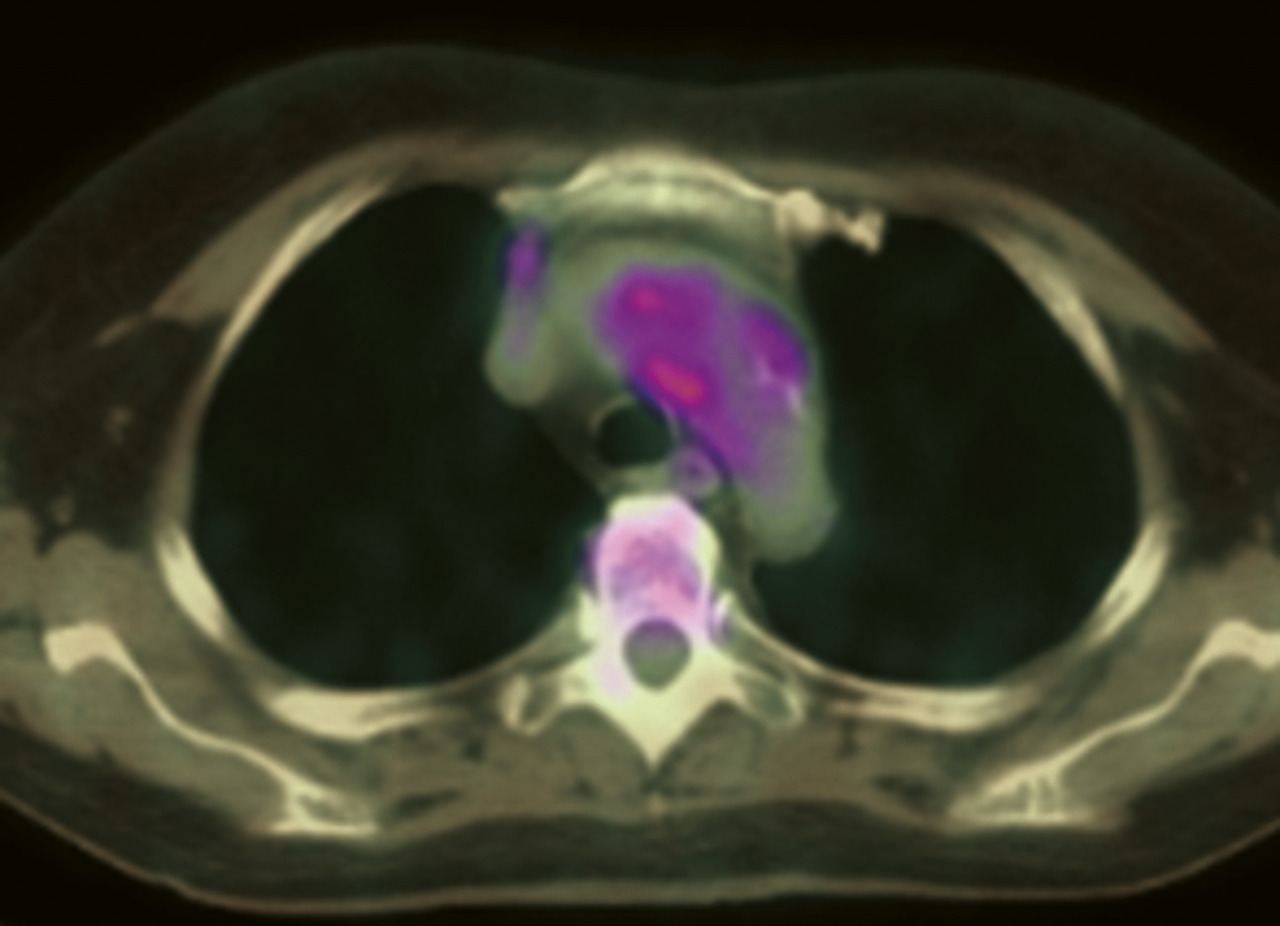

La recherche d’une aortite est recommandée chez tout patient ayant une artérite à cellules géantes. il peut en effet exister des lésions inflammatoires de l’aorte (40 % des cas), parfois associées à une dilatation voire un anévrisme de l’aorte (fig. 2), ce qui imposera une surveillance spécifique. Dans de rares cas, ces anévrismes peuvent être d’emblée compliqués, avec des risques de rupture ou de dissection de l’aorte. La recherche d’une aortite peut se faire par angio-tomodensitométrie [angio-­TDM] (fig. 5), angio-IRM, ou encore par tomographie par émission de positons au 18-F déoxyglucose (TEP) idéalement couplée à une tomodensitométrie (TEP-TDM).

Sinon, une exploration des artères de gros calibre sera faite en cas de signe d’appel clinique (abolition d’un pouls, claudication), par écho-Doppler, angio-IRM, angio-TDM, ou TEP-TDM. Il faut noter qu’au moins 1 de ces 3 derniers examens sera de toutes façons déjà réalisé pour rechercher une aortite. La 18-FDG TEP-TDM est intéressante de ce point de vue car elle permet de visualiser des hypermétabolismes d’origine inflammatoire, tant au niveau de l’aorte (fig. 6) qu’à celui de toutes les autres artères de gros calibre.